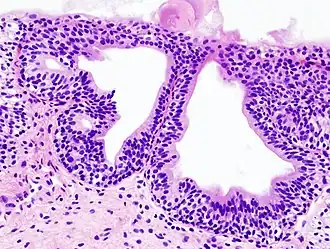

![]() Histopatología de una cistitis glandular en una biopsia citoscópica. Tinción con hematoxilina y eosina. | ||

Puede tener distintas causas. La causa más frecuente de cistitis es la infección por bacterias gramnegativas, destacando entre todas la Escherichia coli. Para que un germen produzca cistitis primero debe colonizar la orina de la vejiga (bacteriuria) y posteriormente producir una respuesta inflamatoria en la mucosa vesical. A esta forma de cistitis se le denomina cistitis bacteriana aguda. Afecta a personas de todas las edades, aunque sobre todo a mujeres en edad fértil o a ancianos de ambos sexos. Otras formas de cistitis son la cistitis tuberculosa (producida en el contexto de una infección tuberculosa del aparato urinario), la cistitis química (causada por efectos tóxicos directos de algunas sustancias sobre la mucosa vesical, por ejemplo la ciclofosfamida), la cistitis rádica (secuela crónica de tratamientos con radioterapia sobre la pelvis), la cistitis glandular (una metaplasia epitelial con potencialidad premaligna) o la cistitis intersticial (una enfermedad funcional crónica que cursa con dolor pélvico, urgencia y frecuencia miccional).